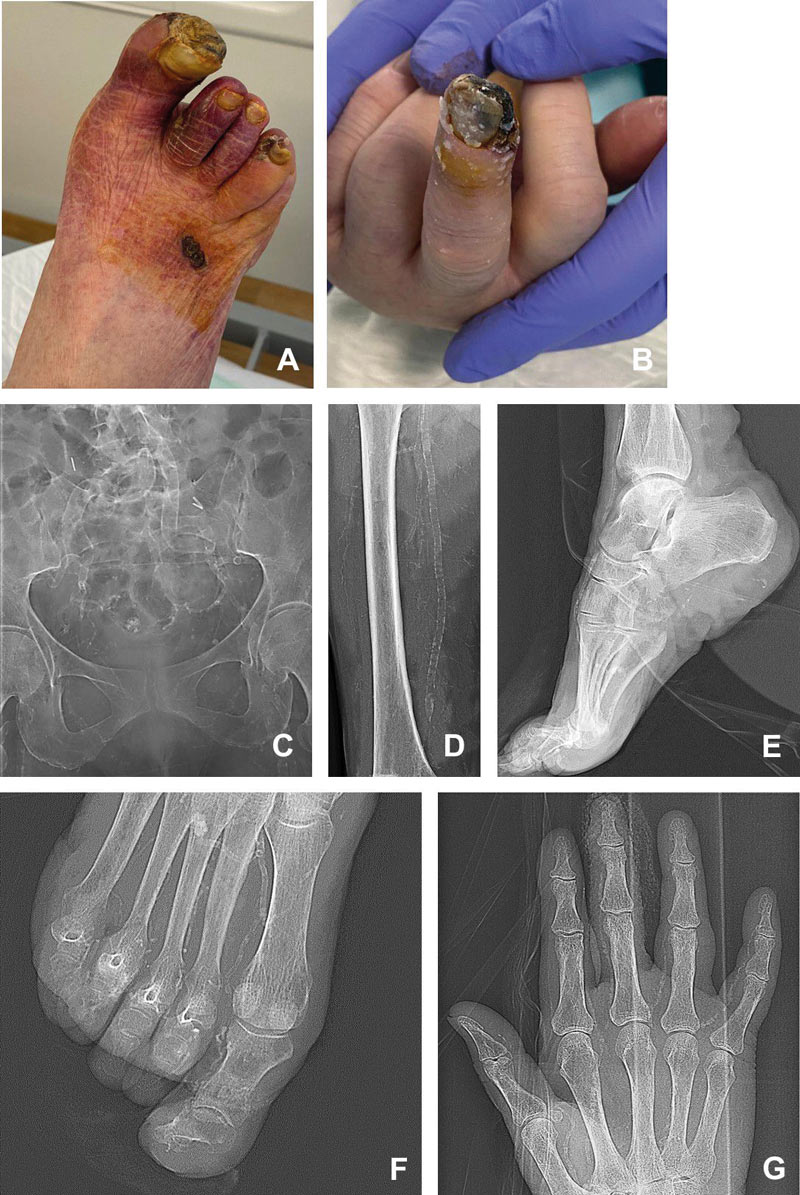

Bei vulnerablen Patienten ist eine optimale Kontrolle der bekannten kardiovaskulären Risikofaktoren vordringlich. Eine medikamentöse Therapie der Mediasklerose ist bisher nicht bekannt. Die bisher durchgeführten klinischen Studien mit einer Reihe von Wirkstoffen, wie beispielsweise mit Phosphatadsorbern, Magnesium, Natrium Thiosulfat, Cinacelet, Biphosphonaten haben keine eindeutigen Vorteile zeigen können. Die Ergebnisse der aktuell durchgeführten klinischen Studien mit Carnosin, N-Acetylcystein, Niclosamid, Metformin u. a. liegen noch nicht vor. Anhand der vorläufigen Ergebnisse der laufenden CALCIPHYX, NCT0495906, Phase 3 Studie erscheint der Einsatz des, allerdings lediglich intravenös zu applizierenden, SNF472 (hexasodium myo-inositol hexaphosphat) vielversprechend. Bei fehlenden etablierten Standards für eine medikamentöse Therapie der Mediasklerose, können derzeit keine verbindlichen Therapieempfehlungen ausgesprochen werden. Ohne ausreichende Evidenz wird bei Patienten mit einer Mediasklerose gelegentlich off-label die Einnahme von Vitamin K2 bzw. Magnesium empfohlen. Bei Patienten mit schweren peripheren Durchblutungsstörungen kommen offene operative und endovaskuläre Revaskularisationen in Betracht. Die Abbildungen 5, 6 und 7 zeigen ein typisches Beispiel eines Patienten mit einer fortgeschrittenen Mediasklerose der oberen und der unteren Extremitäten vor und nach der Durchführung einer endovaskulären Revaskularisation.

Abbildung 5: Mediaverkalkungen bei einer 66-jährigen Diabetikerin; betroffen sind sowohl die Arterien der oberen als auch der unteren Extremität. Dargestellt sind der rechte Fuß mit ausgedehnten ischämischen Nekrosen im Bereich der Zehen und des Vorfußes (A) und die linke Hand mit Nekrose der Endphalange des D3 (B), die nativen Röntgenbilder des Pelvis (C), des rechten Oberschenkels (D), des Fußes im seitlichen (E) und antero-posteriorem (F) Strahlengang sowie der linken Hand (G). (reproduziert mit freundlicher Genehmigung des European Heart Journal).